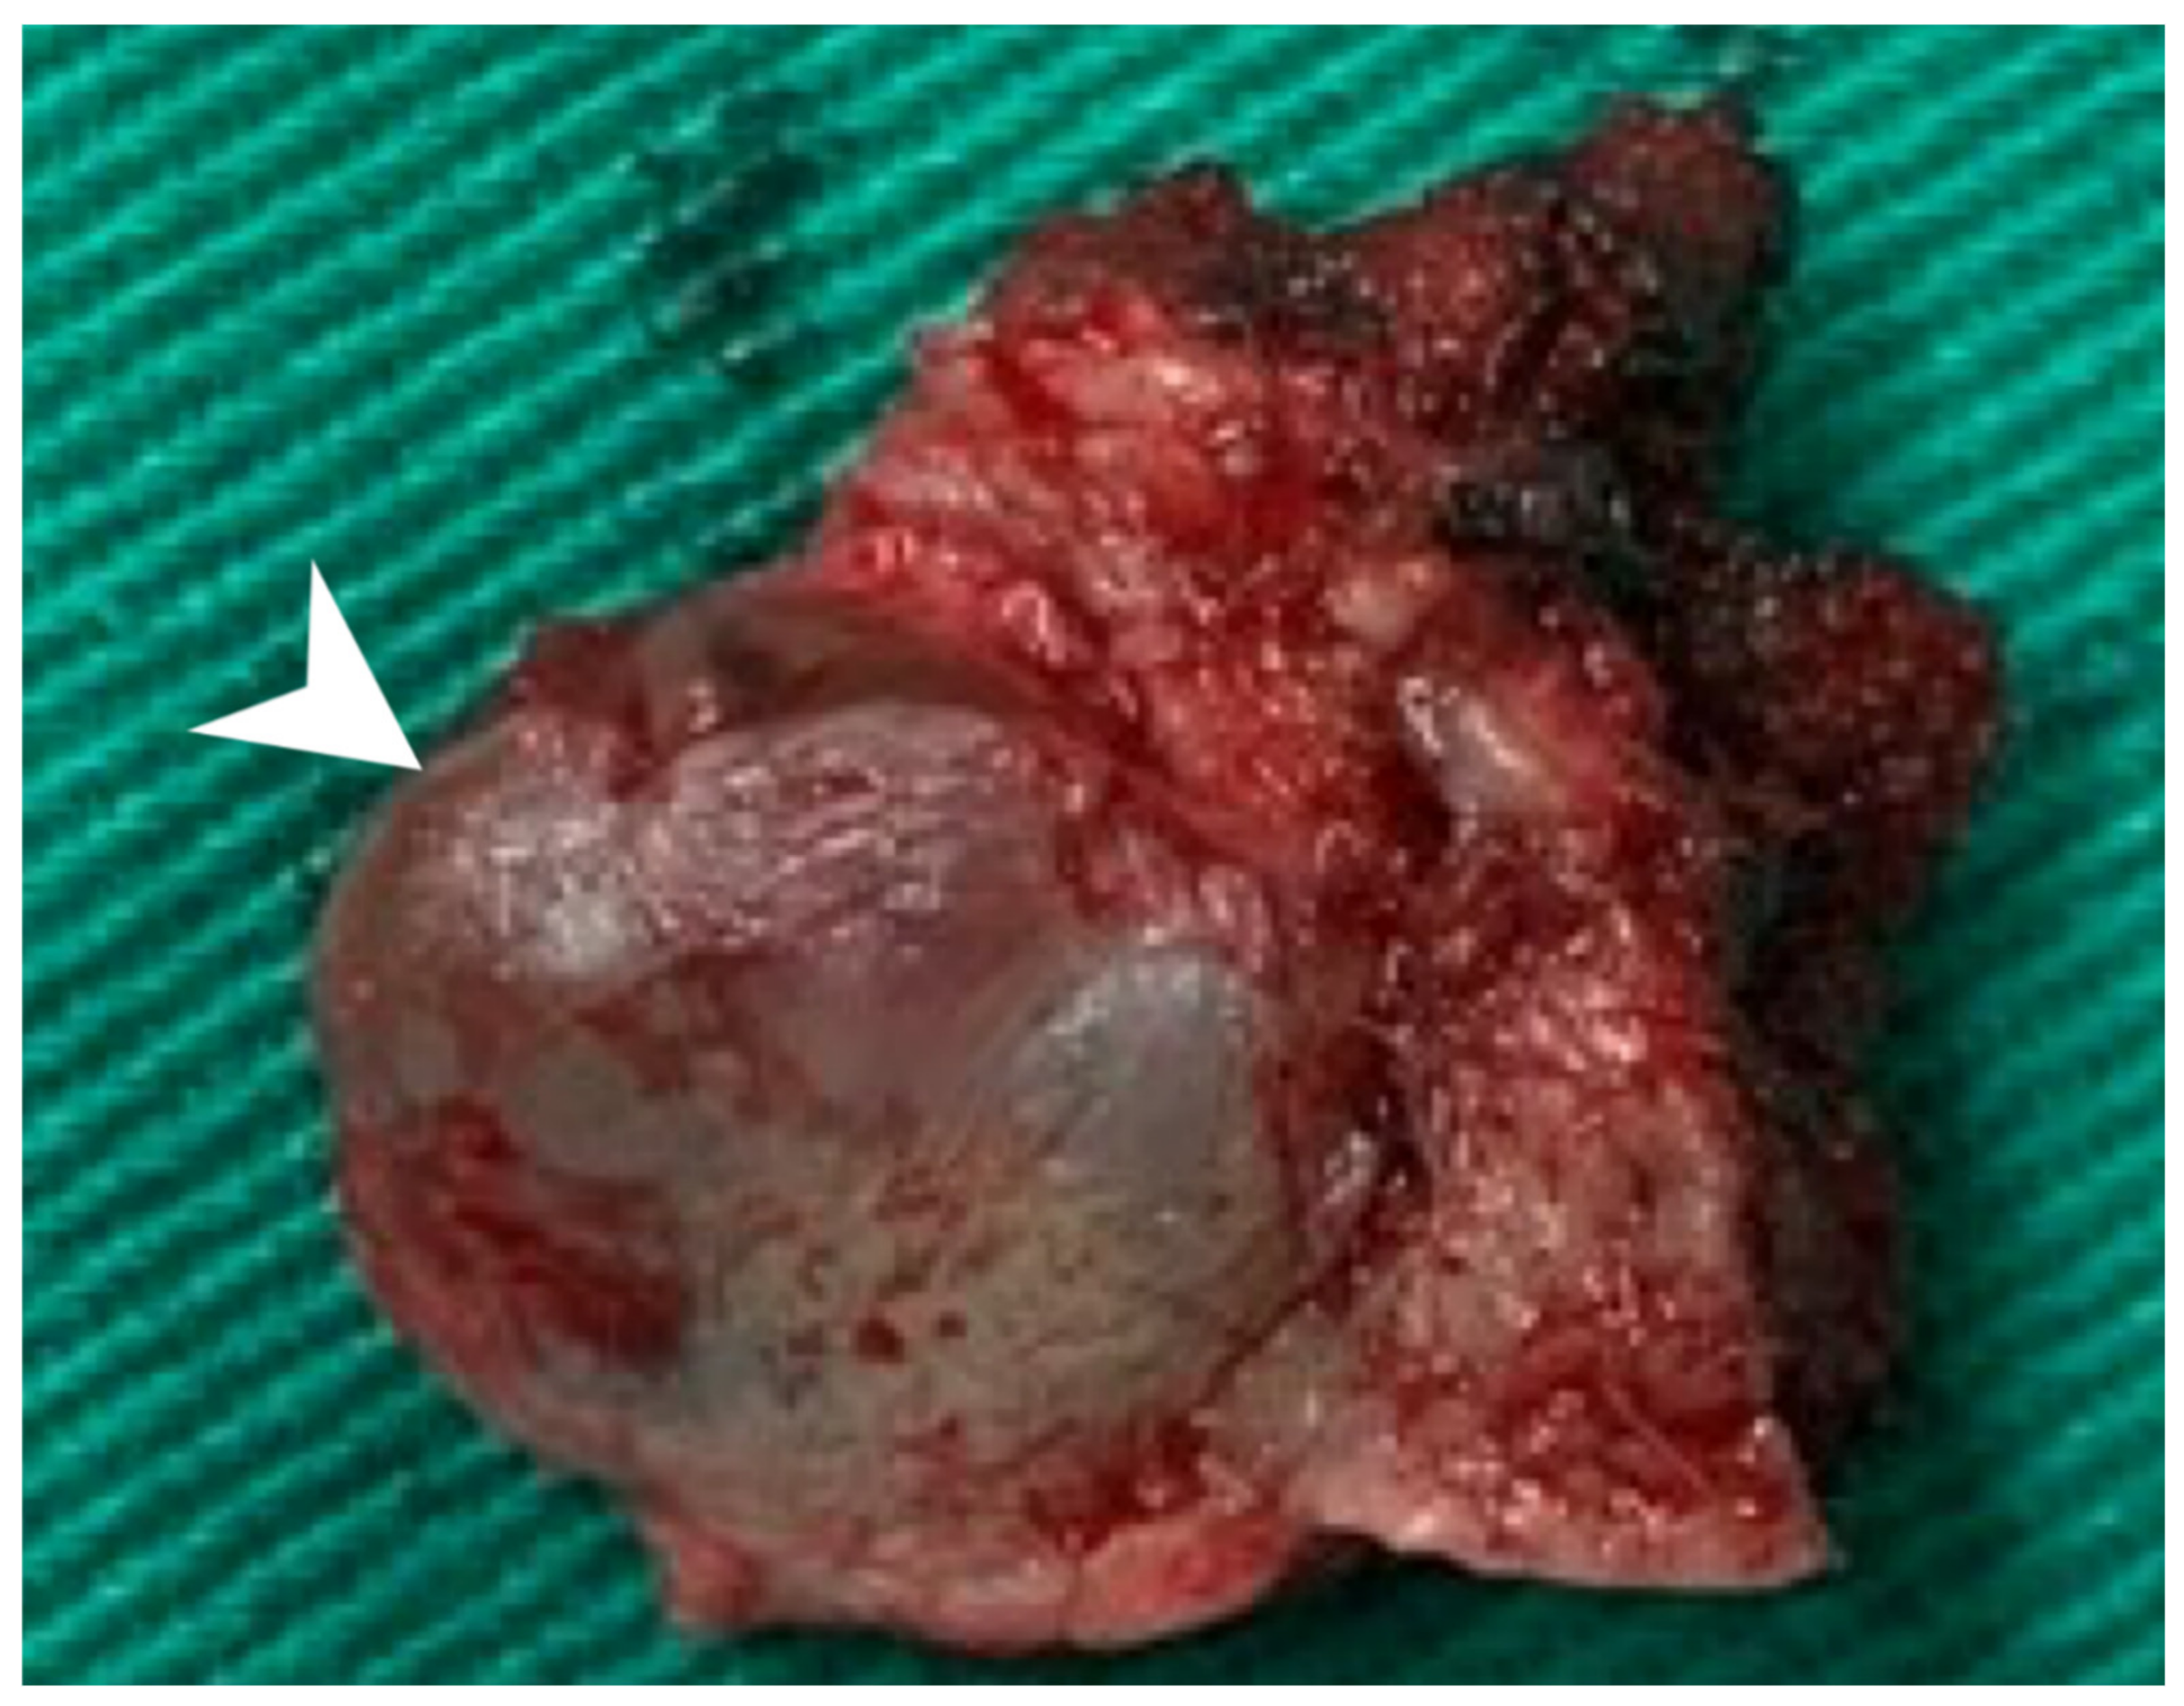

Using an endaural approach, a 1.8 × 1.6 cm EAC tumor was surgically extirpated via canalplasty (Figure 4). A full-thickness skin graft from the posterior part of the auricle was used to cover the skin defect. Histopathological analysis revealed tumor cells in a cribriform pattern (Figure 5A,B). Positive immunohistochemical results were obtained for the androgen receptor (AR; Figure 5C), cytokeratin 7(CK7), G-A-T-A nucleotide-binding protein 3 (GATA3), gross cystic disease fluid protein 15 (GCDFP-15), and human epidermal growth factor receptor 2 (HER2; Figure 5D). The cells were negative for estrogen receptor (ER), progesterone receptor (PR), cytokeratin 20 (CK20), prostate-specific antigen (PSA), and calcium-binding protein soluble in a 100% saturated ammonium sulfate solution (S-100 protein). Therefore, the diagnosis was SDC in the right EAC. Concurrent chemoradiotherapy (CCRT) (featuring a cisplatin-based regimen) was initiated because, although the margin was tumor-free, the tumor came close to the margin. No residual tumor was evident on postoperative positron emission tomography. Further, no tumor recurrence was apparent during the 1-year follow-up.

Figure 4. The 1.8 × 1.6 cm mass with safe margins (arrow).